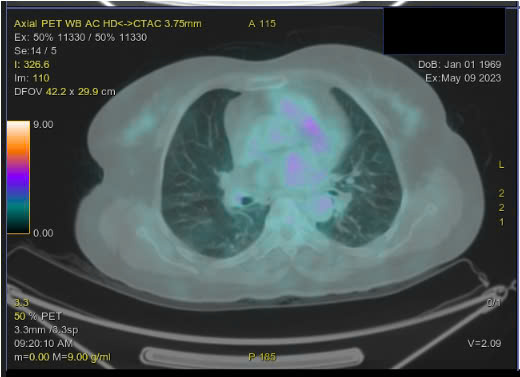

Sau điều trị 4 chu kỳ, bệnh nhân được chụp PET/CT đánh giá đáp ứng điều trị:

Hình 5. Hình ảnh không thấy nốt ở phổi và hạch trung thất (so với phim trước điều trị)

– Không thấy hình ảnh tăng chuyển hóa ở tiểu khung

– Hình ảnh tăng chuyển hóa FDG lan tỏa ở tủy xương đốt sống ngực, thắt lưng, xương chậu 2 bên do phản ứng.

– Hình ảnh vài dải mờ và đám kính mờ phân bố rải rác nhu mô 2 phổi, không tăng chuyển hóa FDG.

Theo thang điểm 5-PS, bệnh nhân có đáp ứng là điểm 1 tại các tổn thương. Bệnh đáp ứng hoàn toàn trên PET/CT.